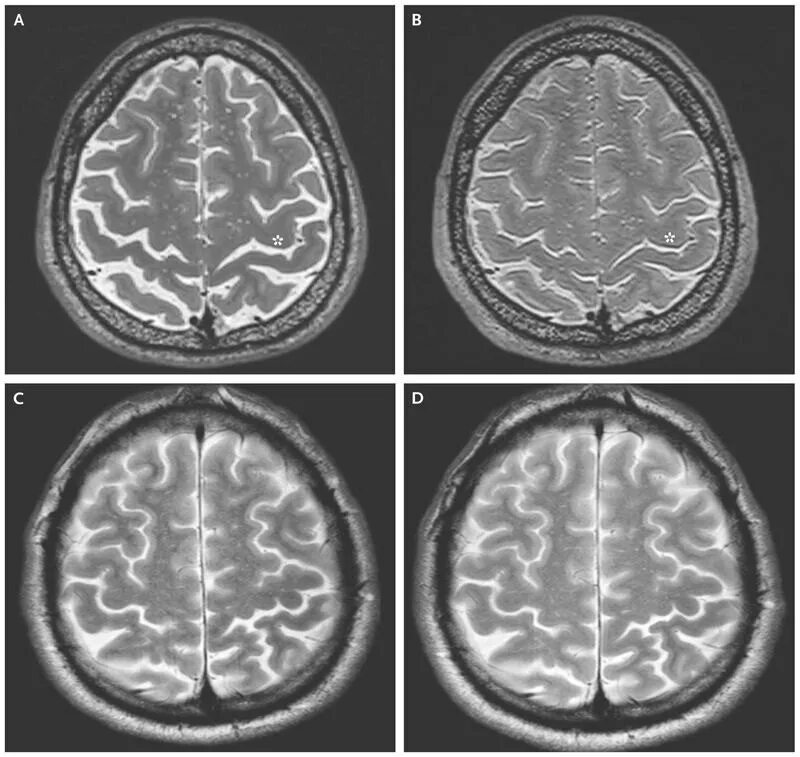

Диффузная активность головного мозга